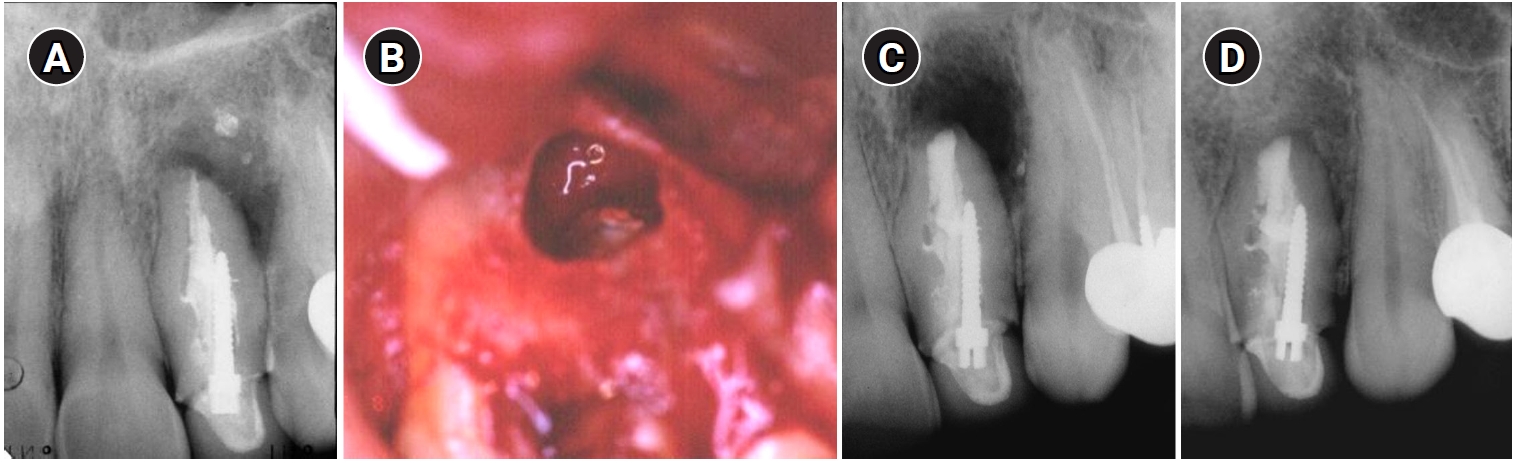

A 13-year-old girl was referred to the endodontic department in 1972, with a diagnosis of DI, pulp necrosis, and a chronic apical abscess in the left lateral maxillary incisor. Nonsurgical root canal treatment (NSRCT) was performed over three visits as described in a previous case report [16]. At the third visit, the tooth was asymptomatic and was obturated with gutta-percha and AH26 cement (DeTrey, Zurich, Switzerland) using the lateral condensation technique. A radiograph taken two years later showed evidence of healing of the periapical radiolucency (Figure 1), and complete healing was observed at the 3-year follow-up, as documented in the case report by Tagger [16].

Thirty years later (2002), the patient came back to the department with a complaint of pain and swelling and was diagnosed with an acute apical abscess in tooth #22. Informed consent was obtained and endodontic surgery was performed in the department (Figure 2). The tooth was treated with a modern surgical endodontic protocol, involving a dental operating microscope: local anesthesia with lidocaine 2% with epinephrine 1:100,000, triangular full mucoperiosteal flap, osteotomy, root-end resection with no bevel using a high-speed bur, curettage, retrograde preparation using ultrasonic tips, and root-end filling with intermediate restorative material (IRM; L.D. Caulk Company, Milford, DE, USA).

Clinical and radiographic follow-up was scheduled annually. Radiographic outcomes were assessed based on the criteria established by Rud et al. [17]. At a 2-year follow-up, the tooth was clinically asymptomatic, with good adaptation of the crown to the tooth and with radiographically normal periapical tissue (Figure 2C). The tooth remained asymptomatic with radiographically complete healing at an additional follow-up visit in 2006 (Figure 2D).